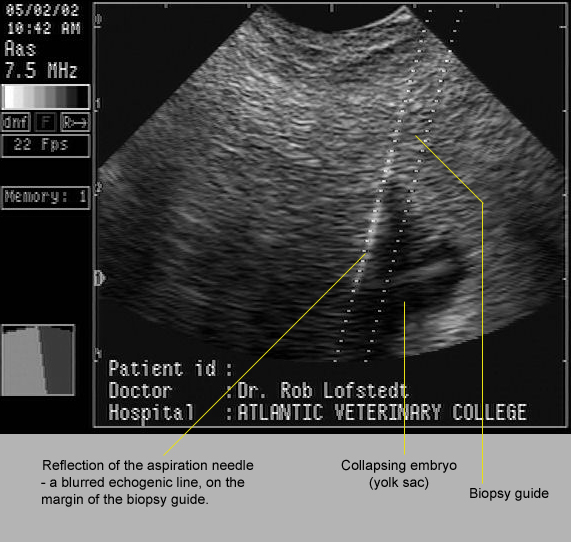

In the image below, 17 day old twins had fixed close to one another within the uterus. One was punctured and drained by ultrasound-guided aspiration through the fornix of the cranial vagina. If one has access to the correct equipment, this is a straightforward procedure.

Image size:571 x 542px